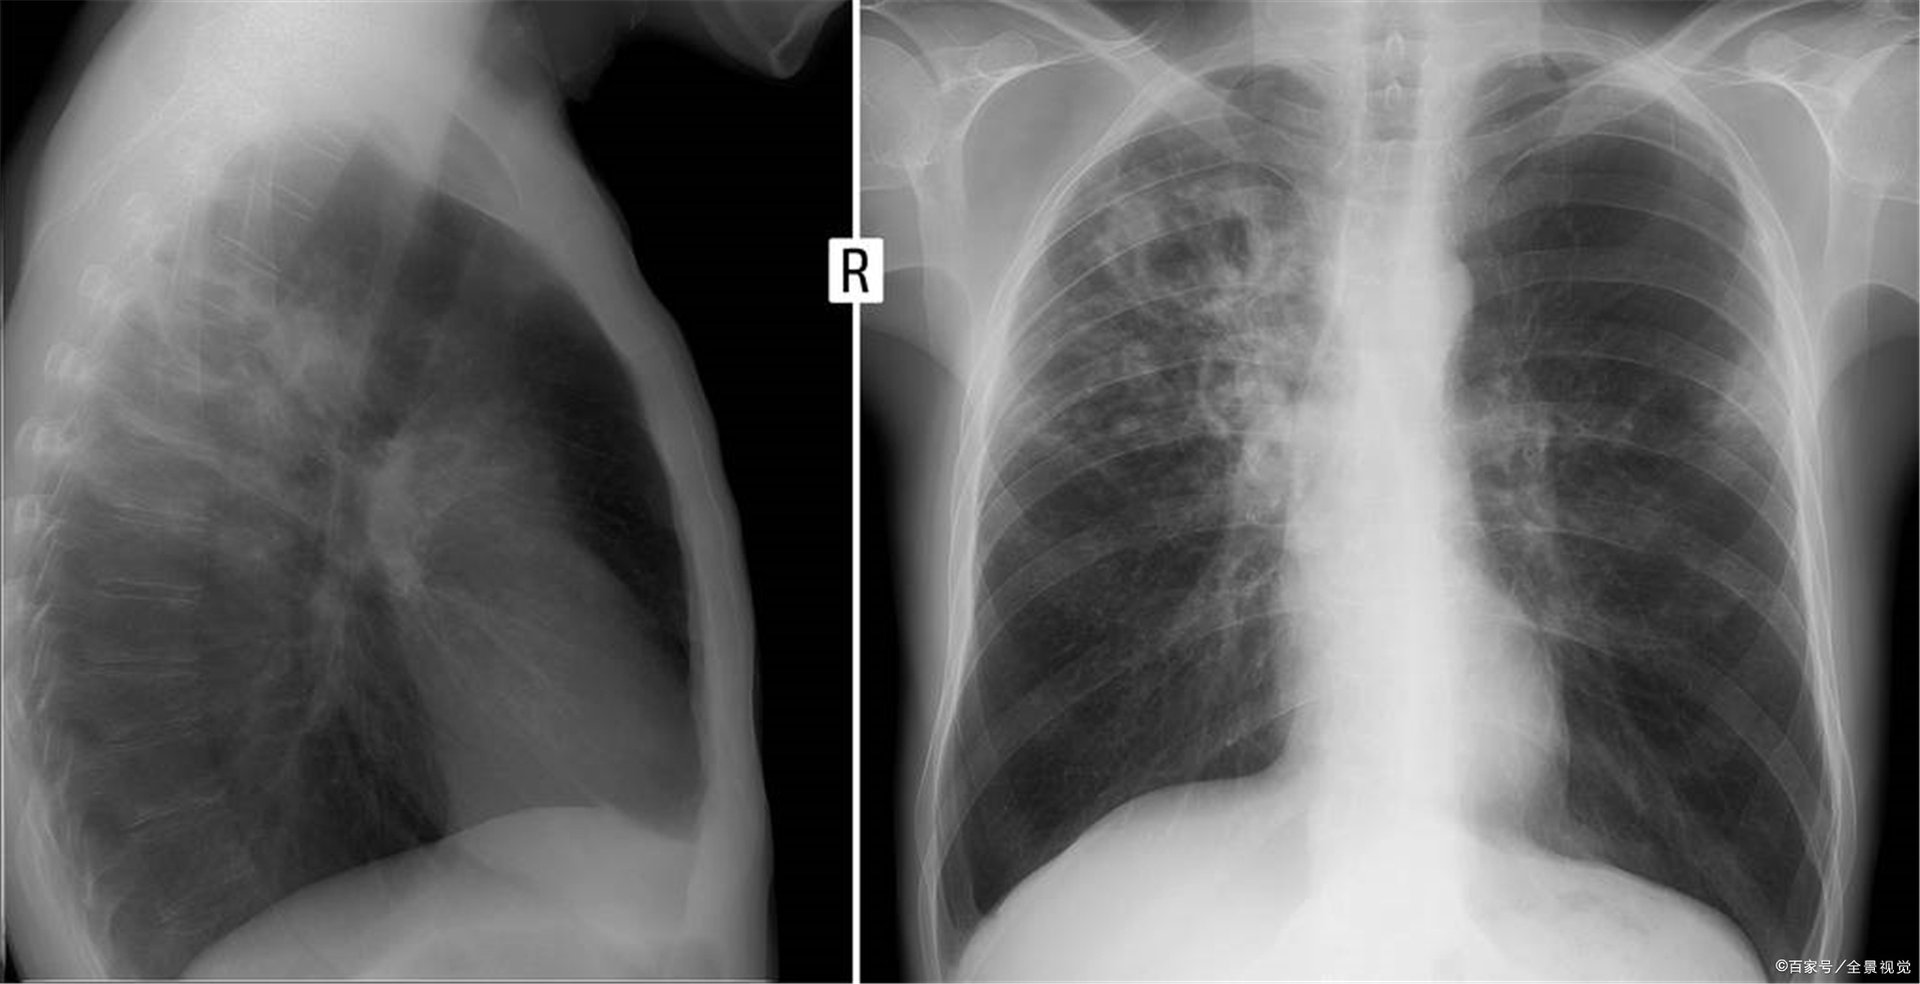

多数患者可能会有阴影,感染灶固定,甚至钙化,其中多数不会复发,也就是不影响正常生活,也就是痊愈,只要少数患者抵抗力下降后可能会复发,千万不可没症状了就不吃药了,那得了全国最好的肺结核医院排名如何呢?